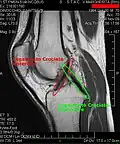

RM de um joelho. -

Os ligamentos são os estabilizadores primários para a translação anterior e posterior, angulação vara e valga, e para a rotação interna e externa da articulação do joelho. O ligamento cruzado anterior (LCA) é a restrição predominante ao deslocamento tibial anterior, pois aceita 75% da força em extensão completa e um adicional de 10% (até 90.º) de flexão do joelho. Com esses dados fica evidente que o LCA é o mais exigido no dia a dia de uma pessoa saudável, que pratica esporte por lazer ou profissão.

| ligamento cruzado anterior (LCA) | dentro | côndilo lateral do fêmur | área intercondilar anterior | O papel do LCA é prevenir o deslizamento anterior excessivo da tíbia em relação ao fêmur |

| ligamento cruzado posterior (LCP) | dentro | côndilo medial do fêmur | área intercondilar posterior | A lesão deste ligamento é incomum, mas pode ocorrer resultando de uma força de tração traumática do ligamento. Este ligamento previne o deslizamento posterior excessivo da tíbia em relação ao fêmur. |